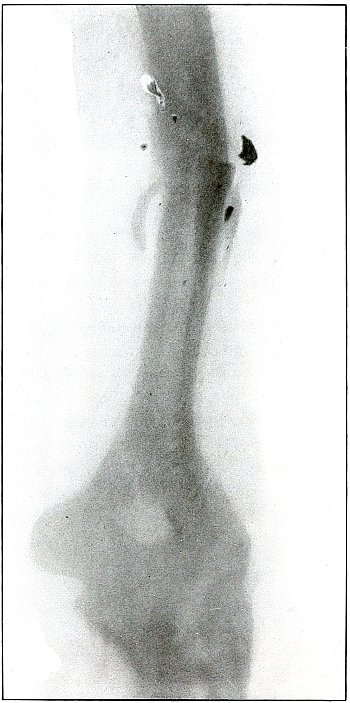

case, showing by callus formation advancing convalescence, reveals

very bad position.

Results as to life and limb are favorable in such cases, but some

deformity is to be expected.

It should be noted that this is a case from Gulhané Hospital, the best

military hospital in Constantinople, where the surgical service, under

Prof. Wieting Pasha, was skillfully conducted.

[Pg 126]

Plate 58.

[Pg 127]

Rifle—Plate 58.

LOWER EXTREMITY.

Gunshot Fracture of the Lower End of the Femur.

The course of the bullet was anteroposterior.

The long, oblique, splitting fracture without separate fragments

indicates the long range of the missile in low velocity.

The wound was infected as is indicated by the drainage tubes in place.

The well-advanced callus formation indicates established convalescence.

Results are favorable for recovery with only fair position and some

shortening.

It may be observed that this is also a case from Gulhané Hospital.

[Pg 128]

Plate 59.

[Pg 129]

Rifle—Plate 59.

LOWER EXTREMITY.

Gunshot Wound of the Left Knee-Joint,

with Lodgment of the Missile in the Joint.

The course of the bullet was transverse, entering the capsule

posterior to the patella without injury to the bone.

As its shadow projection is almost circular, the bullet must be

standing almost on its end pointing toward the plate with its long

axis almost parallel to the line of projection.

As the fibular side of the leg lay next to the plate and as the only

slightly enlarged shadow of the bullet indicates it to be near the

plate, its position is in the joint near the fibular side.

As the bullet is undeformed and its penetrating power very slight, its